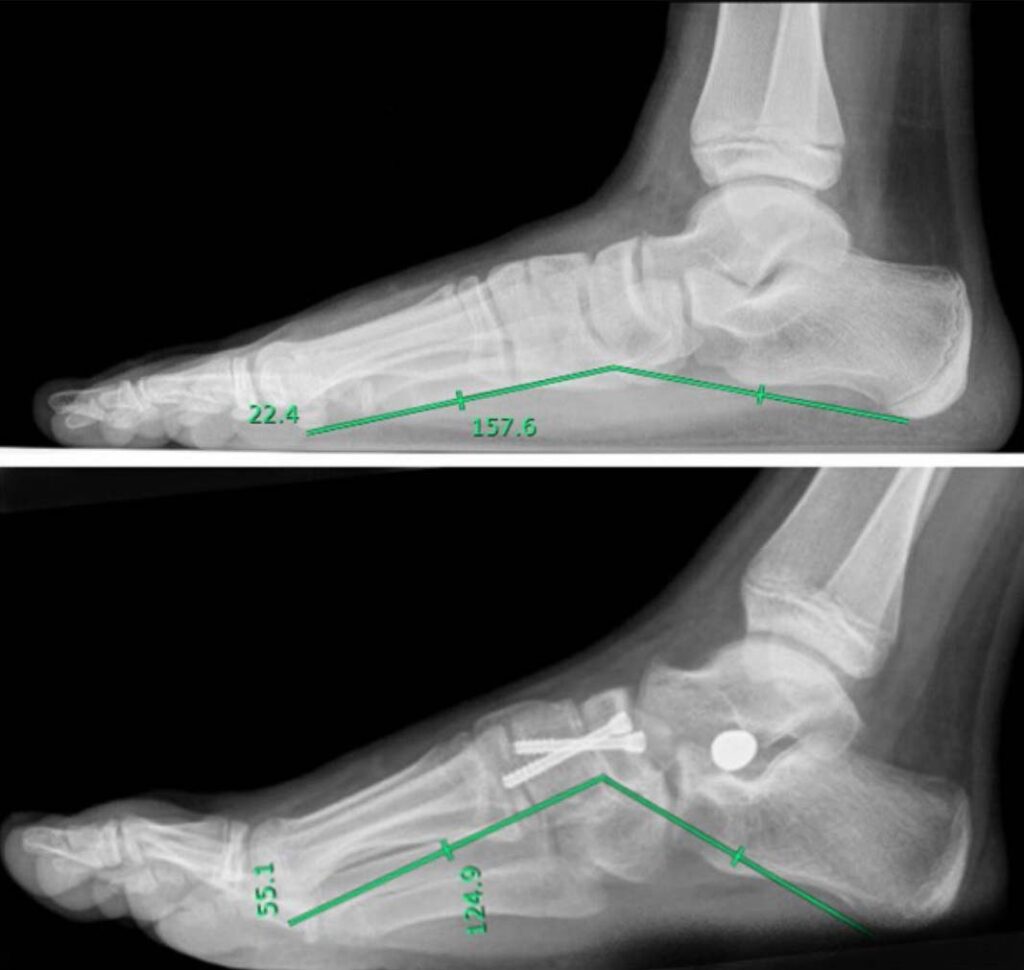

Figure. Evaluation of Costa-Bertani angle in a pre (top panel) and post (bottom panel) surgical x-ray in a right foot. The Costa-Bertani angle is a measurement used to evaluate the stability of the foot’s longitudinal arch. Inclusion criteria for surgery was Costa-Bertani angle >140 degrees.

Although surgical alignment of the rear-foot might be sufficient to achieve acceptable correction of pronation-distortion deformity, concomitant correction of the medial arch might improve functional results.

These authors present experience with combined hind-foot alignment and medial arch reconstruction by in-situ naviculocuneiform arthrodesis for treatment of flexible flatfoot in children. They retrospectively evaluated clinical data available from pediatric (< 18 years old) patients treated for flexible flatfoot in the department of orthopedics at the Villa Aprica Clinical Institute in Como, Italy.

160 surgical corrections of flat foot in 94 children were performed over the study period. Median age was 13 (range, 12–14) years. All patients had a minimum postoperative follow-up of 24 months. Overall postoperative outcomes were optimal in 82% (n = 113/160) of cases, good in 15% (n = 24/160) of cases, and adequate in 3% (n = 3/160) of cases. At 24-month follow-up, complete surgical correction of deformity was achieved in 89% (n = 143/160) procedures. Complete consolidation of arthrodesis was achieved within 3 months from surgery in 84% (n = 134/160) of cases, between 3 and 6 months in 12% (n = 21/160) of cases. There was a significant difference in pre-operative AOFAS score among the different weight categories (P < 0.001). At post-hoc analysis, obese (OB) patients had lower AOFAS versus normal weight or overweight (OW) patients. At 24-months follow-up, there was a significant difference in AOFAS scores among the different weight categories (P = 0.04). At post-hoc analysis, OB patients had lower AOFAS versus OW patients. There was no difference in AOFAS scores at final follow-up (P = 0.12). Postoperative pain was absent in 88% (n = 140/160) of cases.

At a minimum 24-month follow-up, the authors concluded that patients who undergo flat-foot deformity correction using a surgical technique combining sinus tarsi arthroeresis and medial arch reconstruction by naviculocuneiform arthrodesis experience good short-term results.